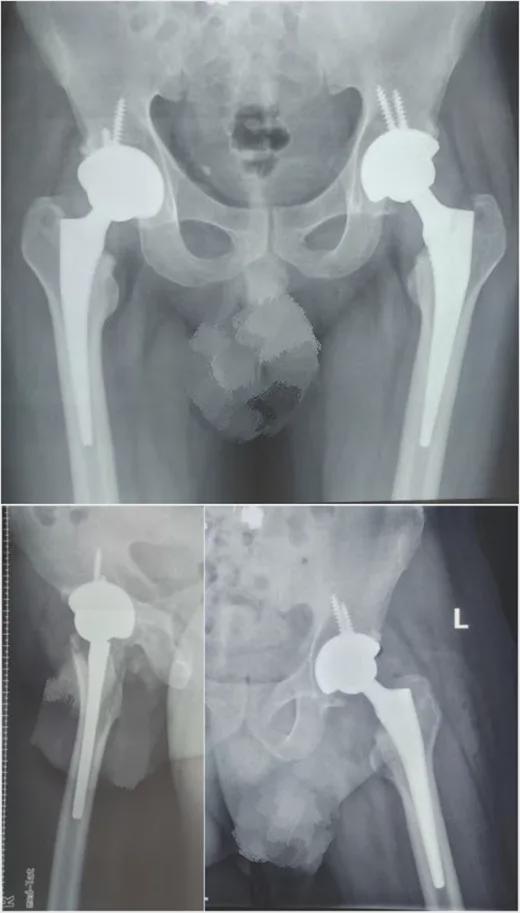

全髋关节置换系统工具,顾名思义,就是用于进行全髋关节置换手术的工具。这种手术主要是针对那些髋关节疾病,如髋关节骨关节炎、股骨头坏死等,导致关节疼痛、活动受限的患者。通过手术,医生会将受损的髋关节替换成人工关节,从而恢复关节功能。

全髋关节置换手术的过程,可以说是相当精密和复杂的。首先,医生会根据患者的具体情况,选择合适的人工髋关节。他们会使用全髋关节置换系统工具,进行手术操作。

手术过程中,医生会先在患者的髋关节部位做一个切口,然后取出受损的髋关节。接下来,他们会将人工髋关节安装到正确的位置,并进行固定。缝合切口,手术完成。